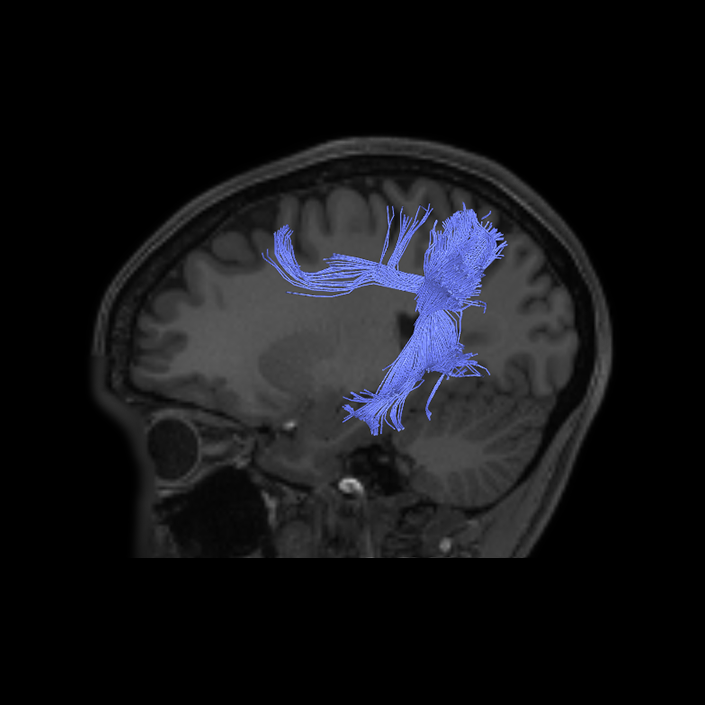

DTI image |

DTI image |

DTI image |

DTI image |

DTI image |

DTI image |

DTI image |

DTI image |

DTI image |

DTI image |

DTI image |

DTI image |

DTI image |

DTI image |

DTI image |